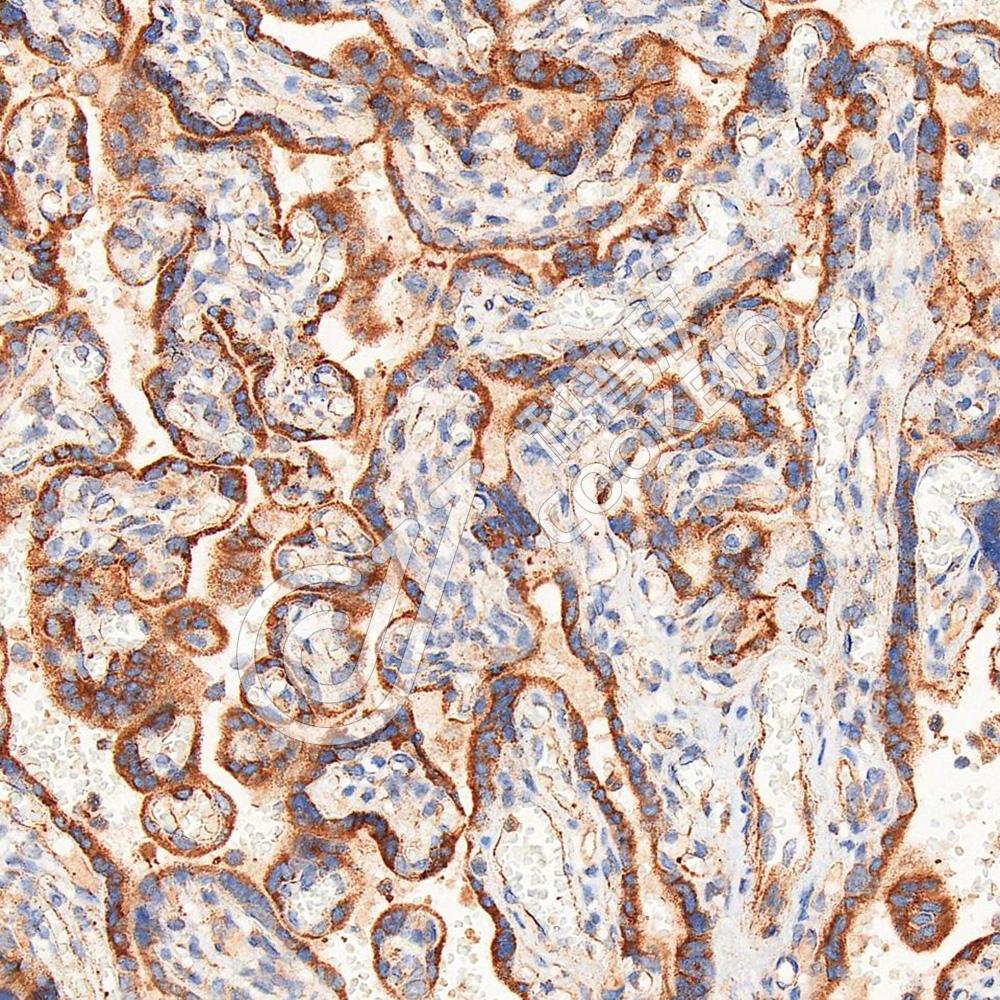

IHC检测MANEA蛋白(货号 K1342513).

样品: 人胎盘, 4%多聚甲醛 (货号KSG1101) 固定12-24小时.

抗原修复: 柠檬酸抗原修复液(干粉, pH 6.0) (KSG1201), 98℃, 20分钟.

—抗: 1: 1800稀释, 4℃ 孵育过夜.

二抗: S-vision免疫组化多聚二抗(山羊抗兔),即用型 (货号KB3906), 室温孵育20分钟.